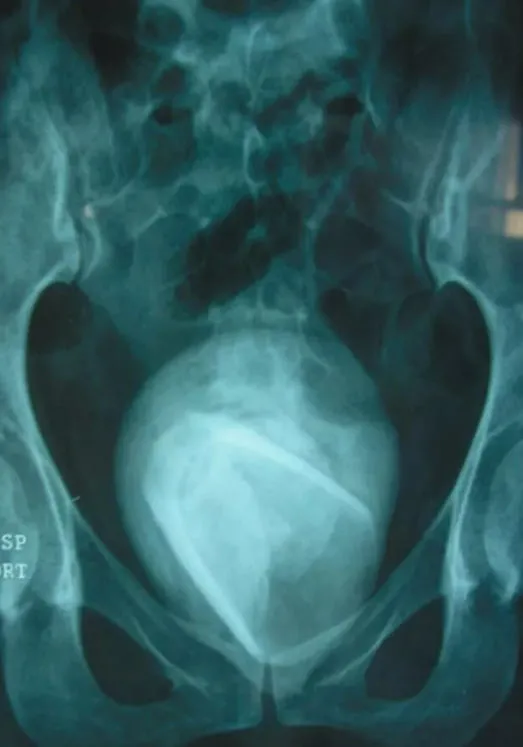

İdrar yolları enfeksiyonu şikayetiyle hastaneye başvuran kadının röntgen filmi çekildikten sonra ortaya çıkanlar görenlerin ağızlarını açık bıraktı.

Yapılan röntgen çekimi sonrası ise cam tespit edildi. Yıllardır duran camın dışı zaman içinde mesane taşıyla çevrildiği için hemen fark edilemedi.

Kadının mesanesindeki cam idrar yollarını tıkadığı için yıllar içinde bardağın etrafı sert mineral kütleler tarafından örtülmüştü. Doktorlar hem mesane taşını hem de 4 yıldır orada duran bardağı çıkarmak için hastayı ameliyata aldı.